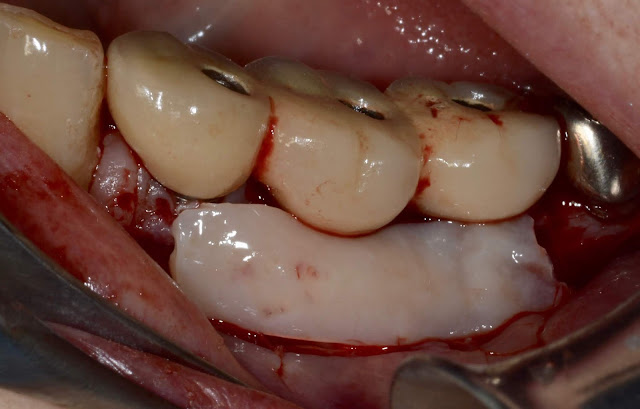

FGG to correct Peri-Implant Mucosal Pain of long-time implant prostheses (>18Y)_ no bone graft